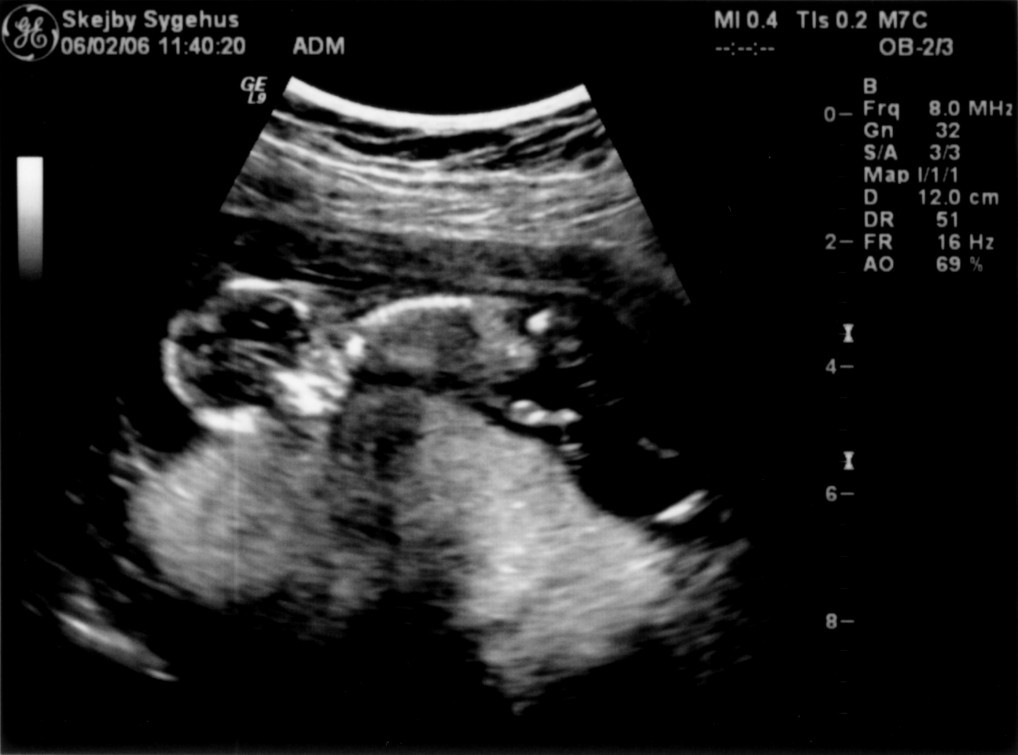

Vi har så endelig været på Skejby Sygehus, hvor specialisterne skulle vurdere babys hjerte. Konklussionen var at baby og hendes hjerte ikke fejler noget - alt er i den skønneste orden. Der blev foretaget en meget grundig skanning og billederne blev vurderet af en afdelingslæge, en overlæge samt en overlæge med mange års international erfaring i børns hjertefejl. Det var en stor lettelse at hun ikke fejler noget. Baby blev undersøgt generelt en gang til at specialisterne og alt er som det skal være. De kunne desuden konstatere, at det er en pige... Du kan se de billeder vi fik fra skanningen herunder.

Baby ligger med hovedet nederst i midten og kigger op. Hun flekser så meget i ryggen at hendes ben går helt op over hovedet. Babys hjerte med nogle målinger.